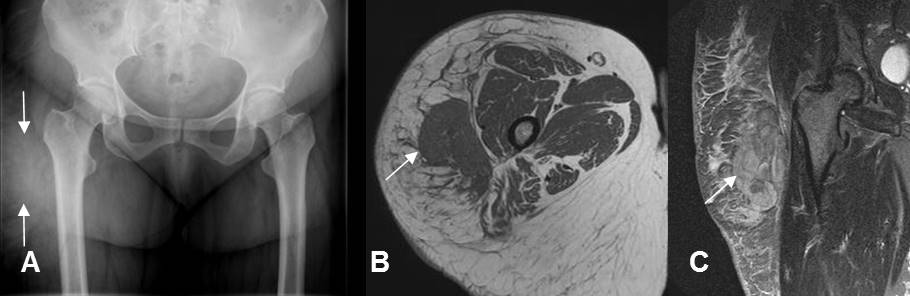

Fig 153. Miositis osificante.

A: Rx de cadera y B: TAC axial. 2 casos diferentes donde existe calcificación de tejidos blandos en relación con grupos musculares, por miositis osificante.